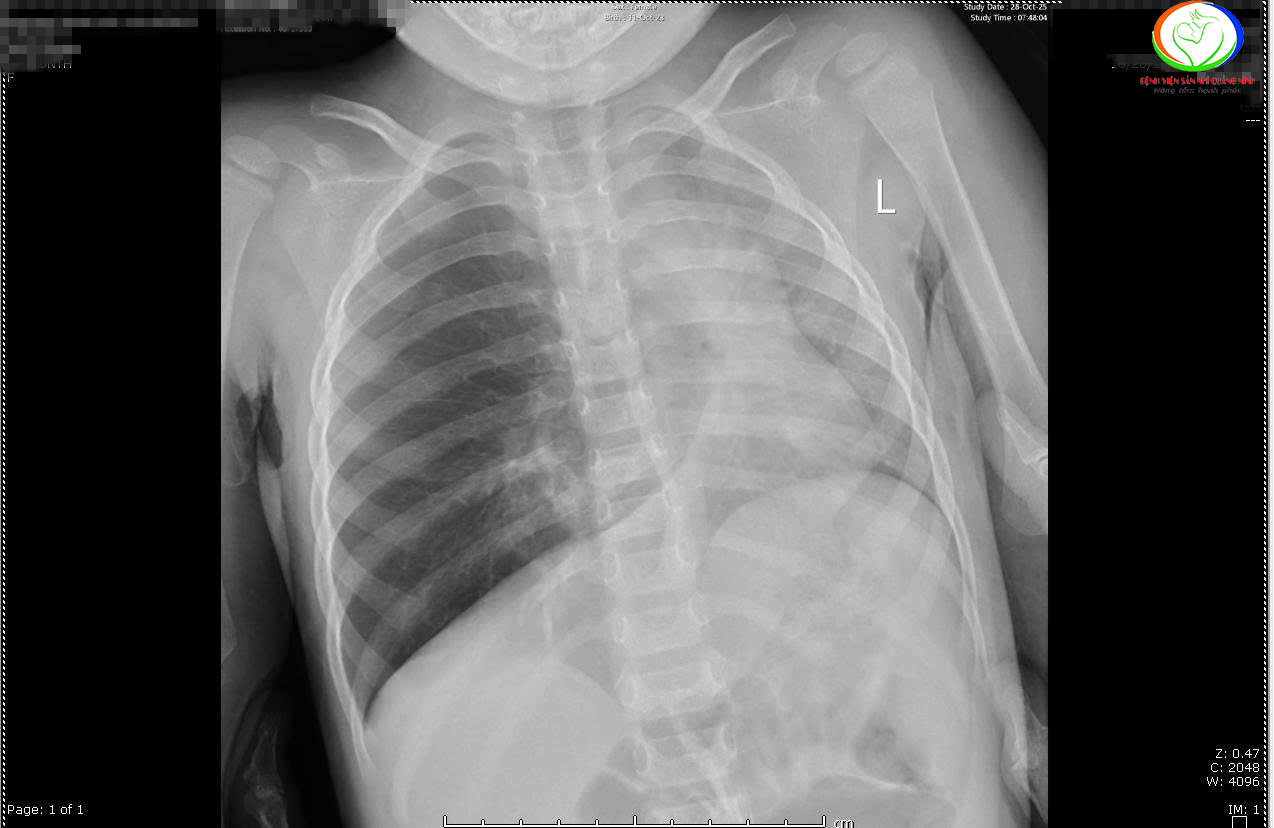

Qua phim chụp X –quang cho thấy các trẻ có hình ảnh ứ khí, mờ quanh rốn phổi. Riêng bệnh nhi N.N.L phổi trái giảm thể tích, kém sáng, xẹp phổi dạng dài thùy dưới phổi phải. Các bác sĩ đã hội chẩn khẩn cấp và chỉ định nội soi khí thanh phế quản cấp cứu gắp dị vật cho trẻ.

Kết quả nội soi ghi nhận tại phế quản gốc phải bệnh nhi N.N.L có dị vật hạt lạc kích thước 0,5×0,7cm, gây bít tắc hoàn toàn phế quản gốc phải; Còn bệnh nhi Đ.M.A, dưới dây thanh khoảng 3cm phát hiện có dị vật mắc trong khí quản là mảnh xương cá kích thước 1,5x1cm gây xung huyết niêm mạc, xuất hiện dịch, phù nề thanh quản.